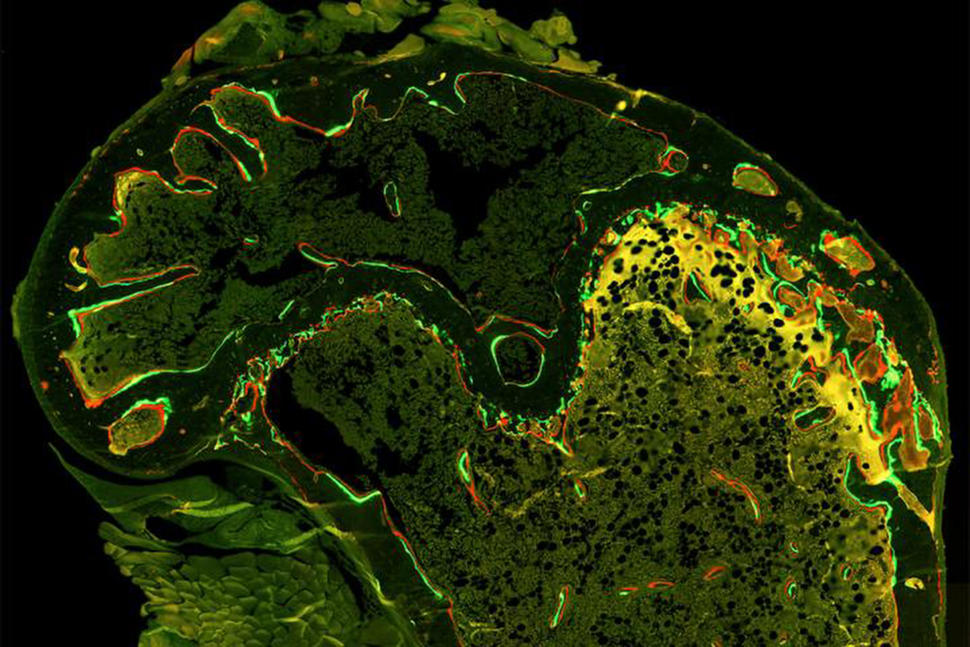

To investigate the role that senescence and this condition might play in bone loss associated with chemotherapy, the researchers first treated mice with two commonly used chemotherapy drugs, doxorubicin and paclitaxel. Some mice also received radiation to a leg.

All three treatments induced the process of cellular senescence, and senescent cells were present in the bones of the mice, the researchers reported.

“Our results support the idea that chemotherapy-induced senescence and the biological effects of this process lead to increased activity by osteoclasts, which can lead to thinner or weaker bone,” said Dr. Stewart.